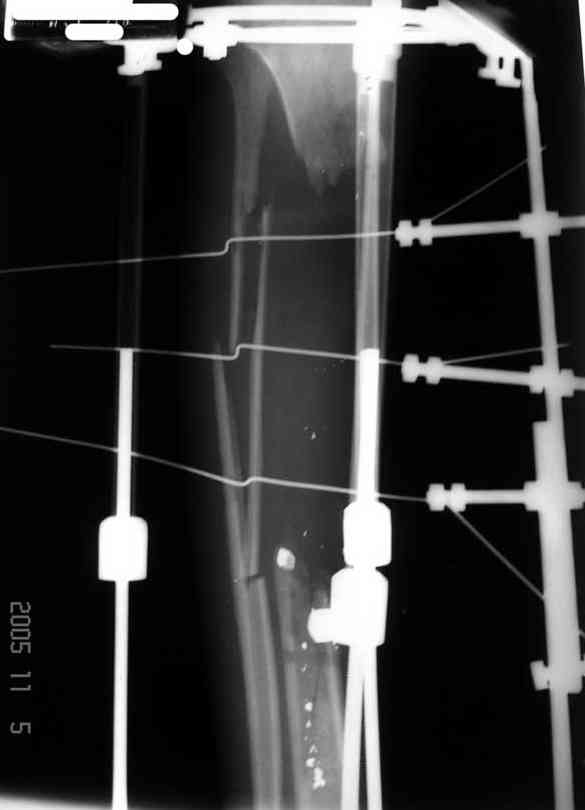

5. Ну и чтобы не быть голословным. Молодой человек подорвался на фугасе (Чечня, 2005 год). Свежие рентгенограммы:

Соответственно ожоги и дефект мягких тканей, переломы костей стопы и пр. Наложили аппарат

Илизарова (как придется), хирургически обработали и героически заживляли мягкие ткани с многочисленными кожными пластиками. В итоге через полгода я принял его вот таким: